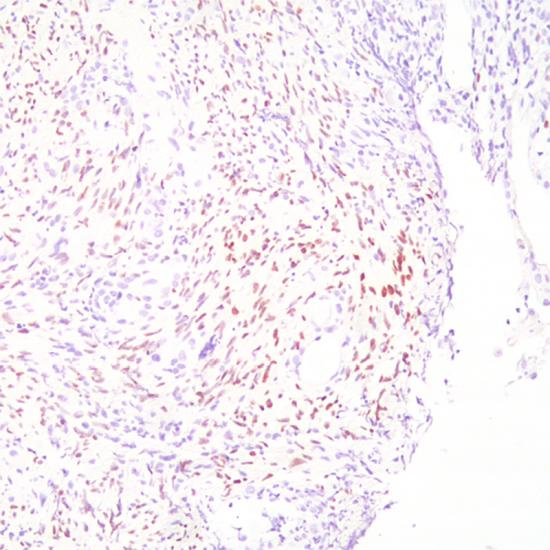

人皰疹病毒8型(HHV-8)抗體試劑(免疫組織化學(xué)法) 閩廈械備20190058號(hào)

• 陽(yáng)性部位:

細(xì)胞核

• 陽(yáng)性對(duì)照:

卡波西氏肉瘤

人皰疹病毒8型又稱作卡波西氏肉瘤相關(guān)皰疹病毒,HHV8感染最早發(fā)現(xiàn)于獲得性免疫缺陷綜合征和卡波西氏肉瘤,后來(lái)也見于原發(fā)性滲出性淋巴瘤、MCD淋巴結(jié)和外周血單個(gè)核細(xì)胞及多發(fā)性骨髓瘤骨髓樹突狀細(xì)胞。